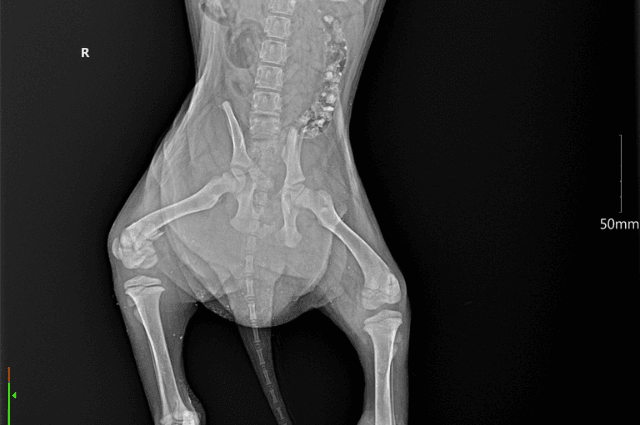

That look of pain and helplessness is unforgettable. One puppy begged with his eyes, the other curled up as if to disappear from the world that had hurt him so much. The surgeries were difficult and now titanium screws and plates hold their little legs together.